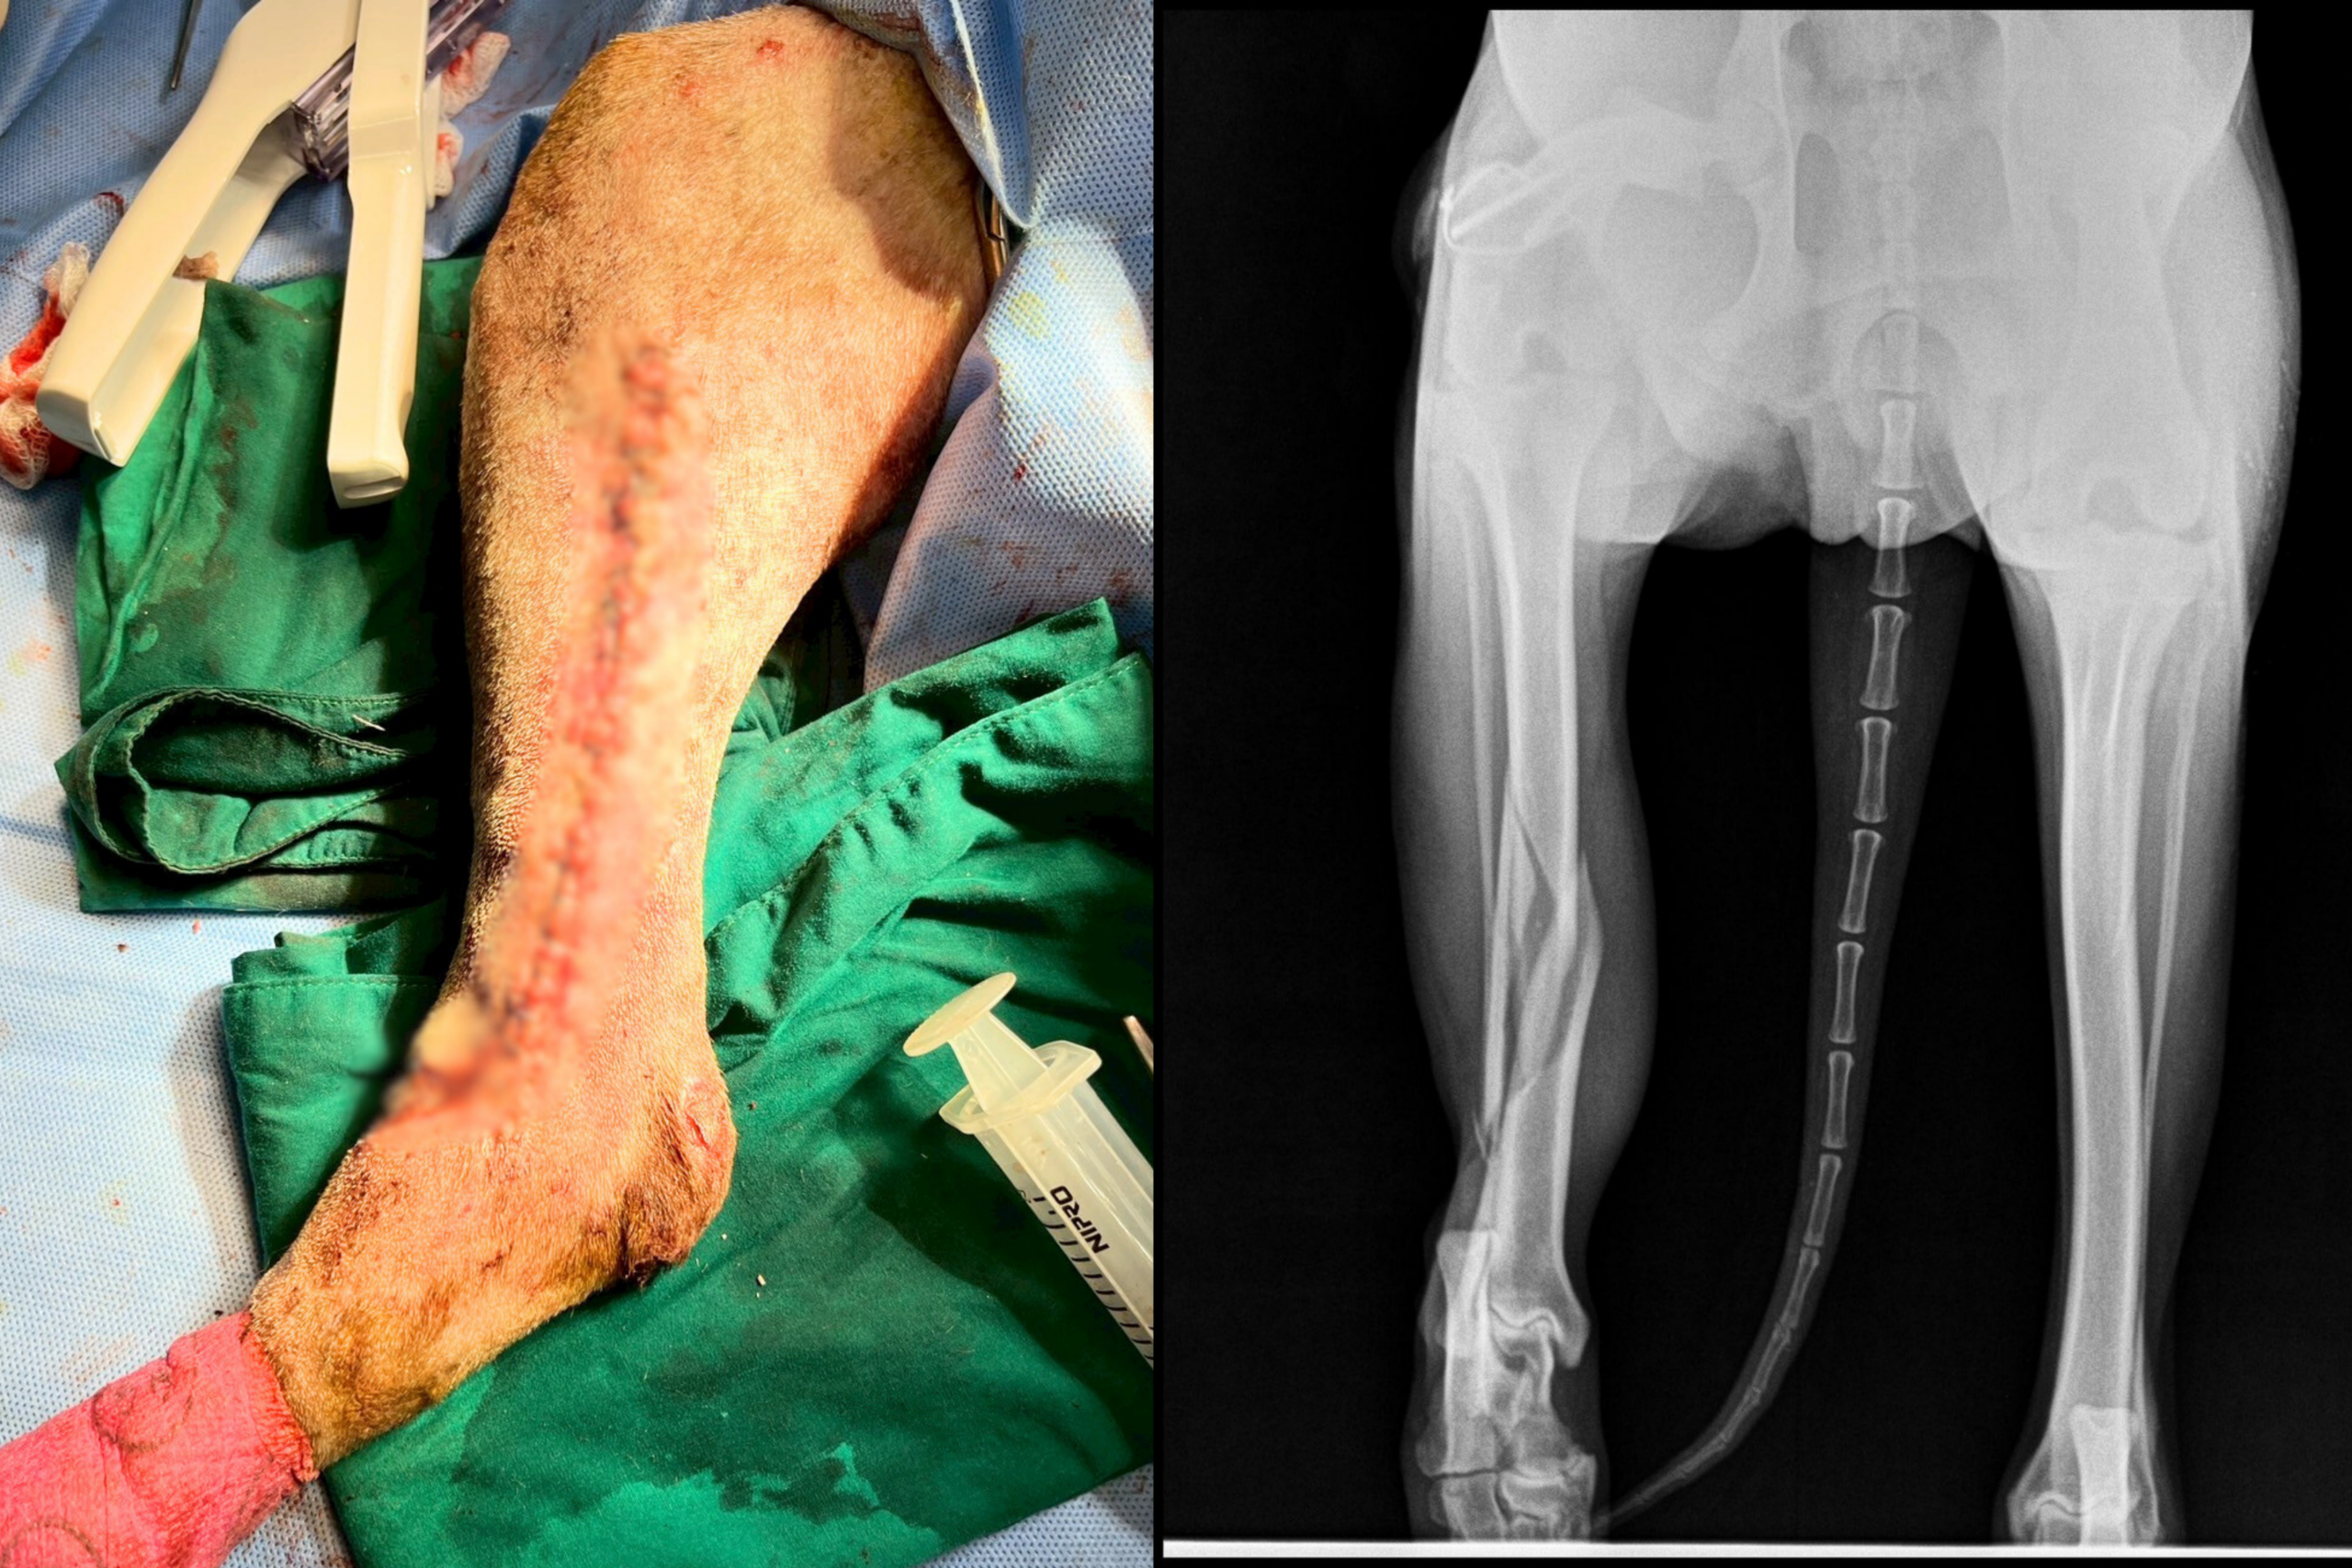

น้องปอม” สุนัขพันธุ์ไทยน้ำหนัก 27 กิโลกรัม ถูกนำตัวเข้ารับการตรวจรักษาที่โรงพยาบาลสัตว์ วิทยาลัยสัตวแพทยศาสตร์อัครราชกุมารี มหาวิทยาลัยวลัยลักษณ์ หลังประสบอุบัติเหตุถูกรถชน ทีมสัตวแพทย์ได้ทำการ เอกซเรย์ (X-ray) พบว่า กระดูกหน้าแข้งข้างขวา (right tibia) ของน้องปอม หักแบบเกลียวบริเวณกลางกระดูก (Spiral fracture at midshaft of right tibia) ซึ่งเป็นการแตกหักจากแรงบิดที่ทำให้กระดูกแตกเป็นแนวเกลียว

สัตวแพทย์จึงวางแผนการรักษาด้วยการ ผ่าตัดใส่แผ่นเหล็กตรึงกระดูกและมัดลวดพิเศษทางการสัตวแพทย์ (medial plate and cerclage wire) เพื่อให้กระดูกยึดติดแน่นในแนวที่ถูกต้อง ช่วยให้น้องปอมสามารถฟื้นตัวและกลับมาใช้ขาได้ตามปกติในอนาคต